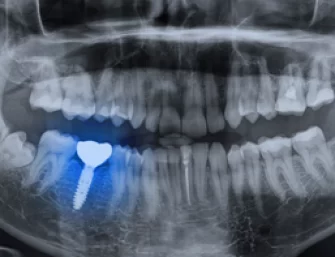

“I have just had my dental implants fitted the whole procedure went really smooth,...”

“I had my dead tooth broken so implant was the only option to make...”